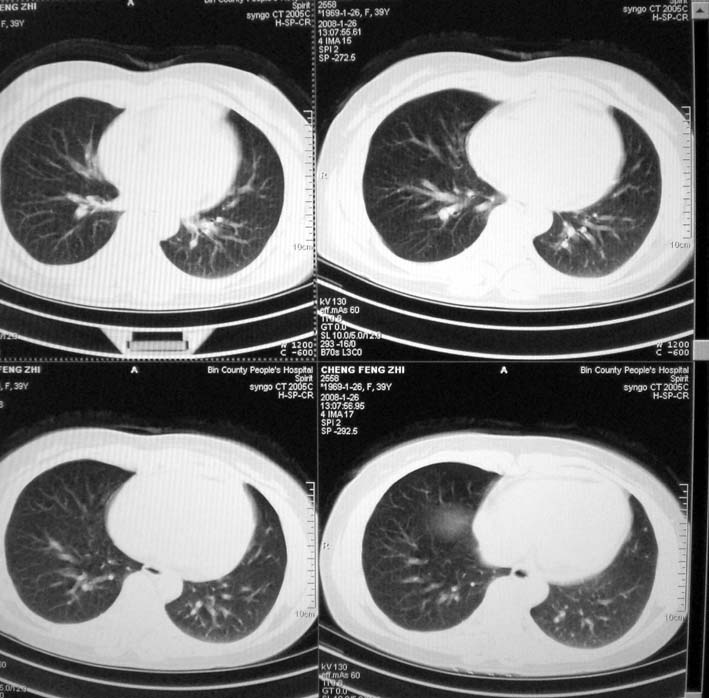

以下是引用guoke在2008-1-27 14:15:00的发言:[br]纵隔增宽,纵隔内血管境界不清,心包积液,考虑纵隔淋巴瘤.[br]

以下是引用随光逐影在2008-1-27 15:52:00的发言:[br]1)考虑为:淋巴瘤。建议:行进一步检查。2)心包积液。